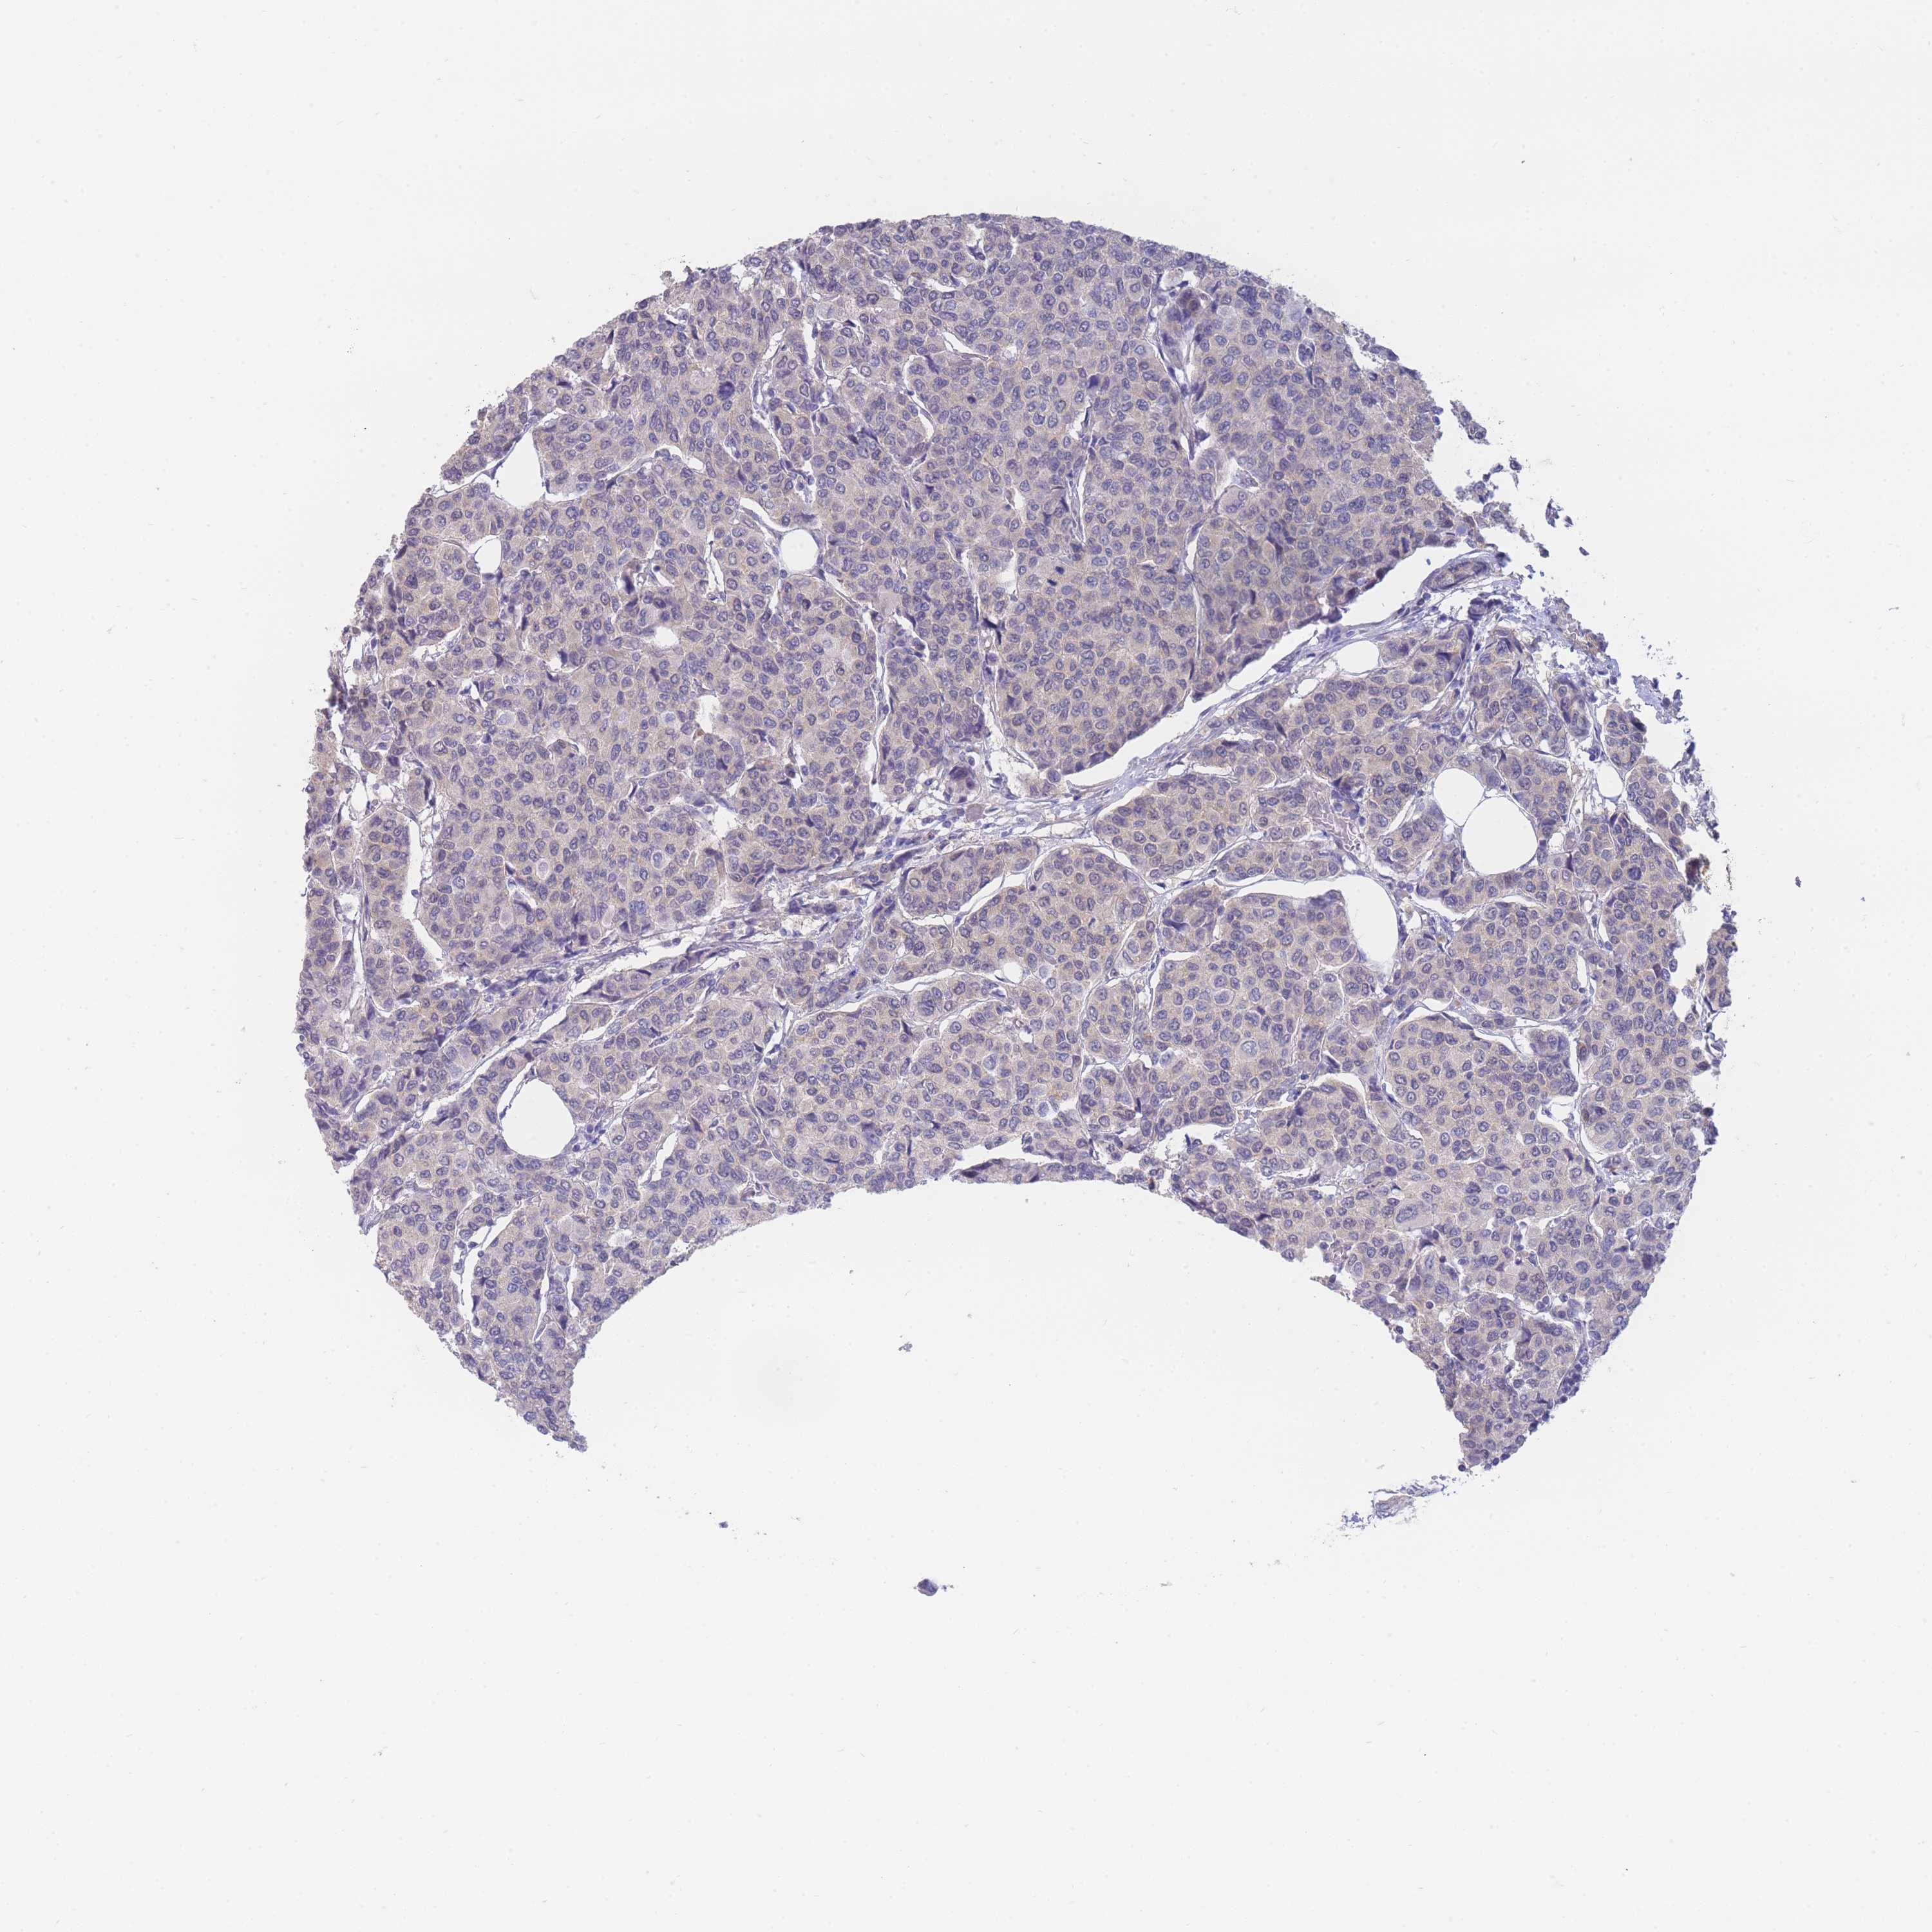

BRCA TCGA BRCA VALIDATION PROTEIN EXPRESSION